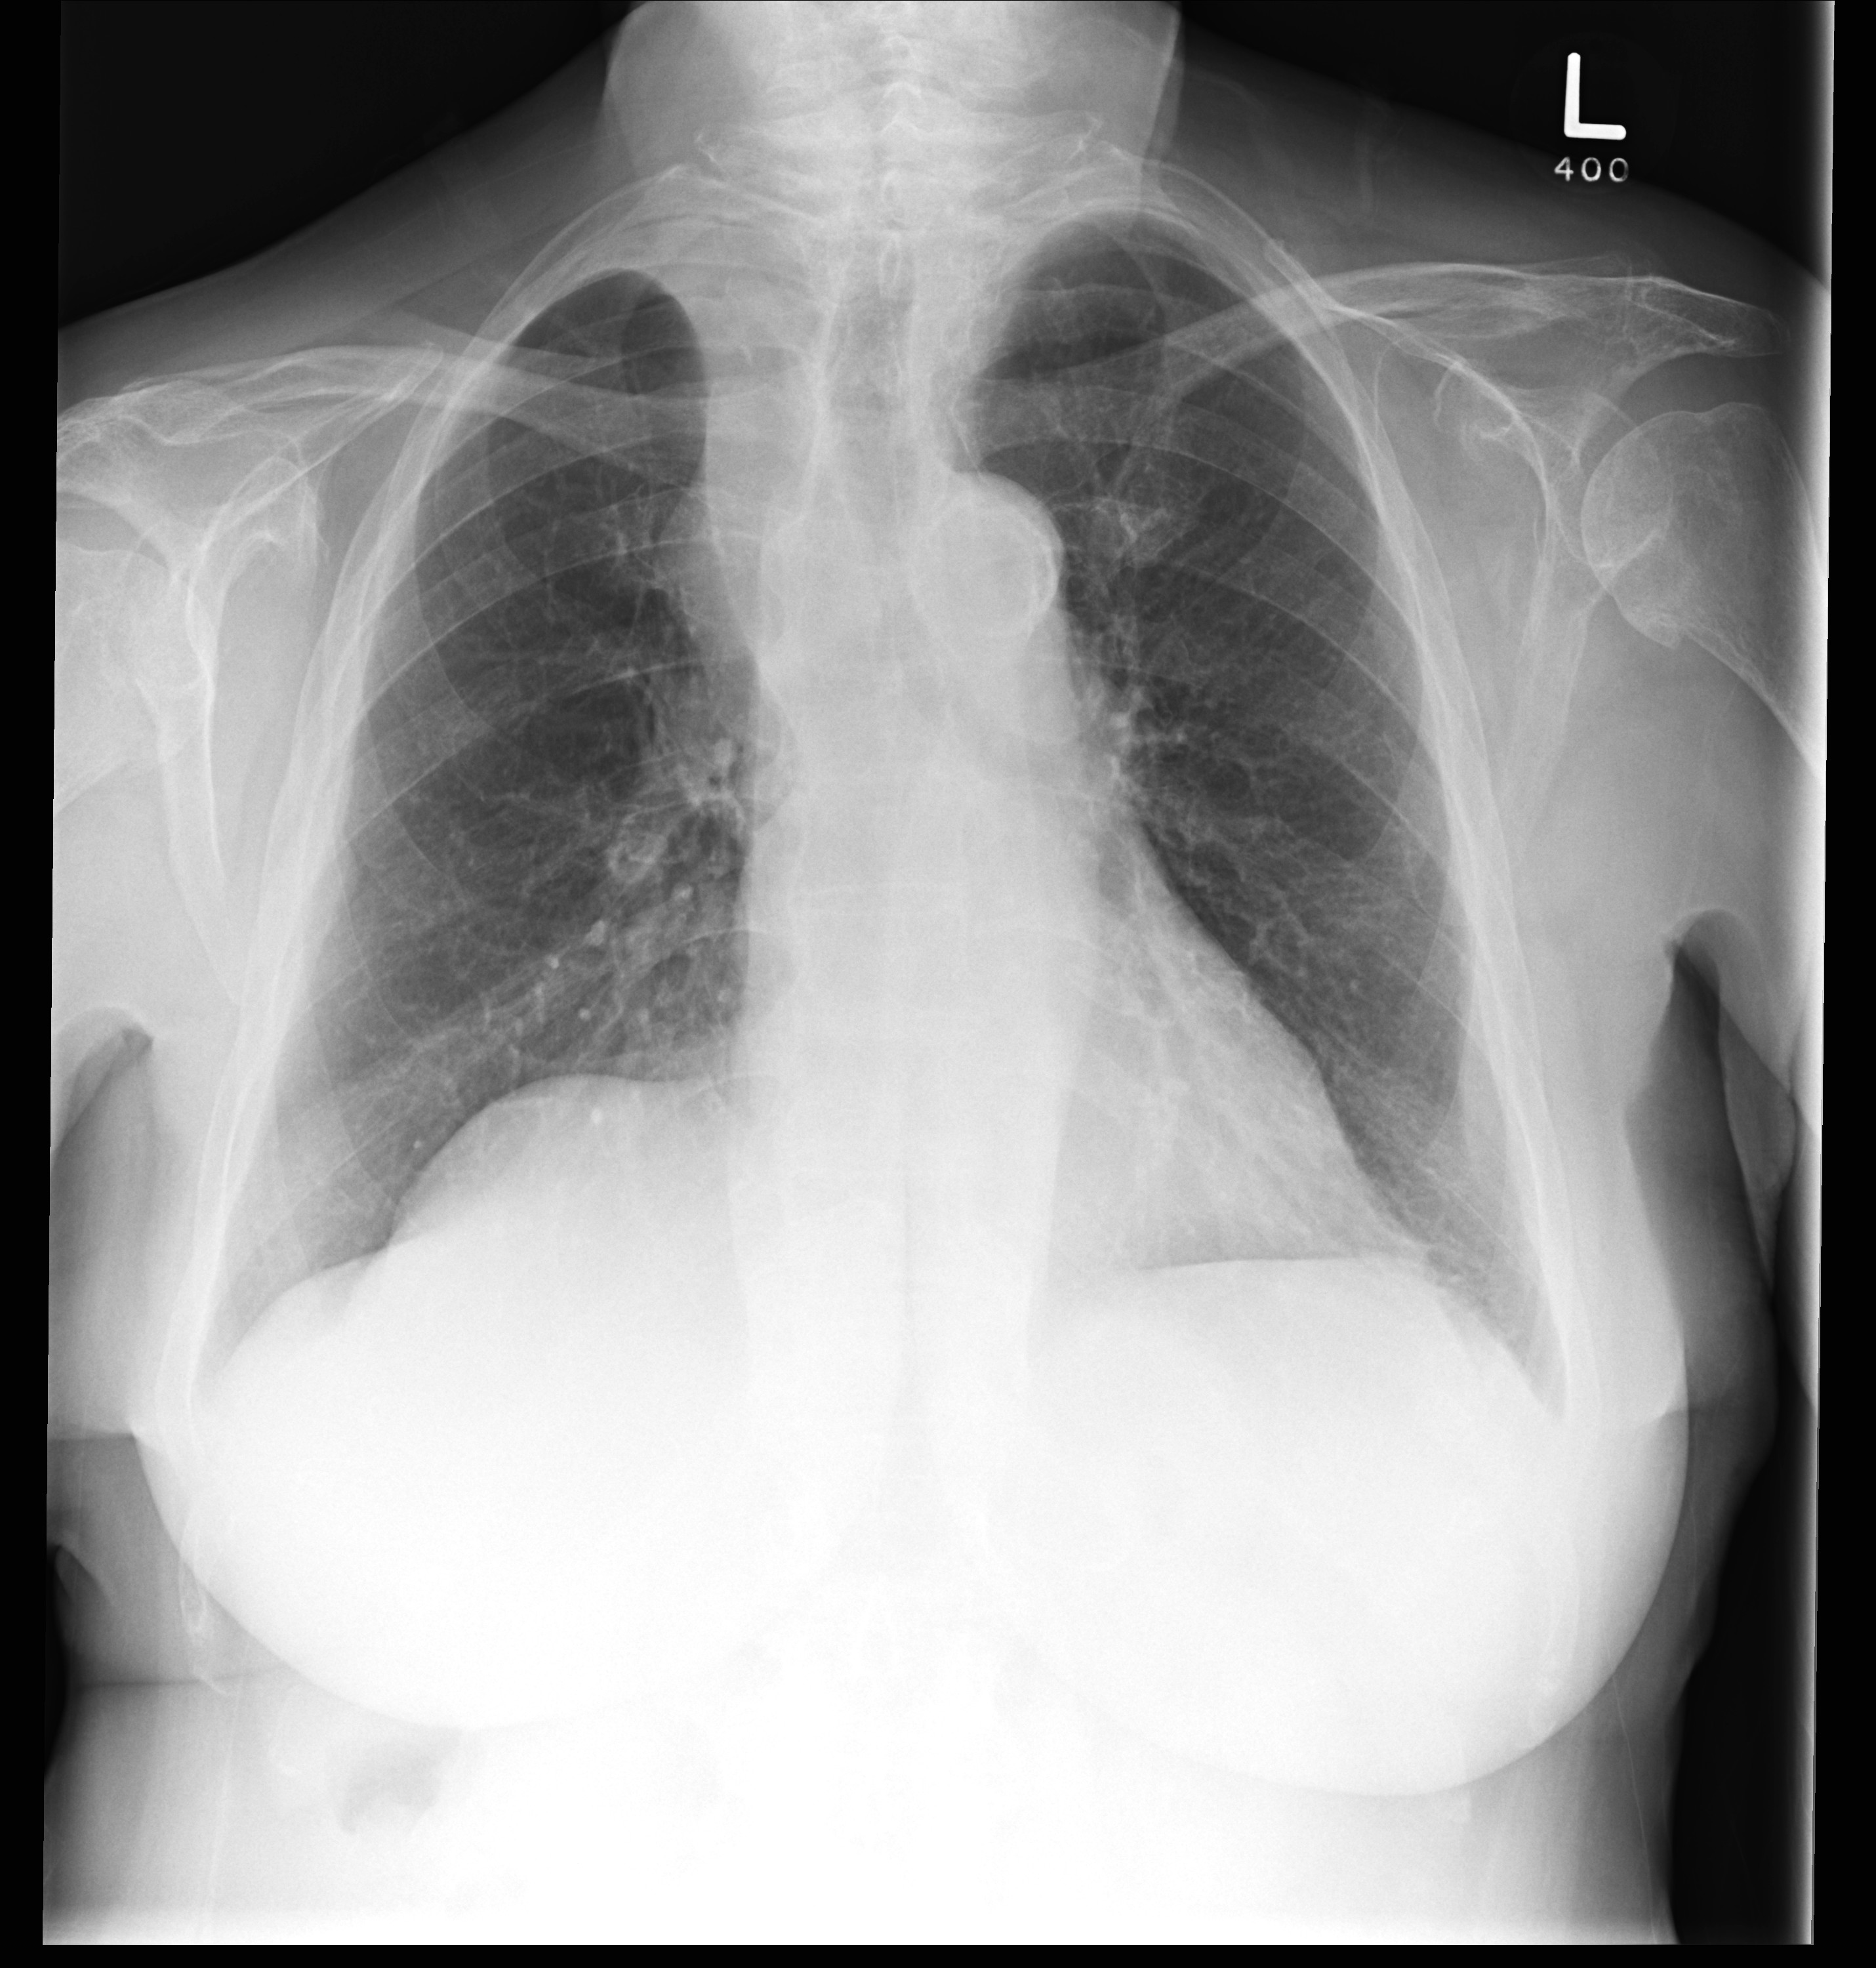

Lobar Collapse

RUL Collapse

RUL collapse Case 10